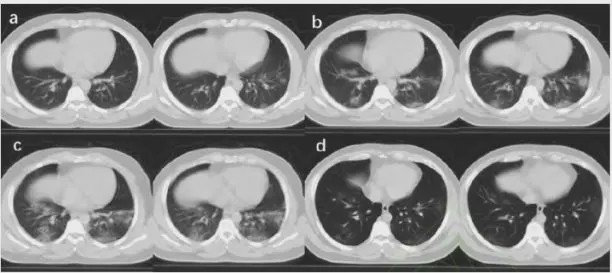

涉嫌剽竊的CT圖片來源於另一篇論文(並可在右下角見知網水印)

伊麗莎白注意到,王文展示的該病人的CT影像的最後一圖,也就是展示病人CT影像有所好轉的那一幅,上面有不明的綠色水印。後來,伊麗莎白髮現該圖實際上直接出自前面提到的張朱文,那個綠色水印是中國知網的水印。顯然王文截圖時也沒管這些小節。(據伊補充,有人問了被截圖的原作者,原作表示根本不知道自己圖被人截走了發表。)